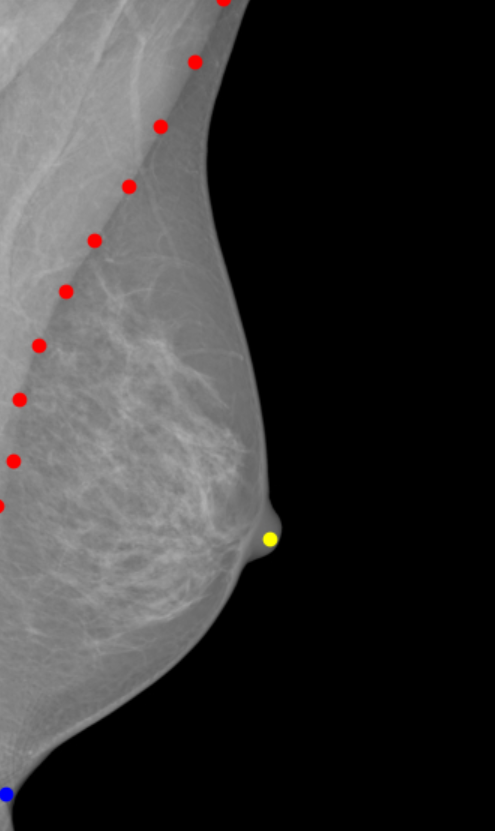

Our primary focus is cancer detection, but good image quality is a vital component in this process, and we are therefore developing methods to assist and improve analysis and image quality. Key factors to image quality are image blur, tissue density and breast positioning within the images. Presently, we are looking into the latter, breast positioning, and developing deep learning graph convolution models that can identify significant areas in the breasts. These models can aid radiographers in assessing mammogram quality, and are able to provide immediate feedback during imaging, for instance if key points are missing or a breast is positioned incorrectly.